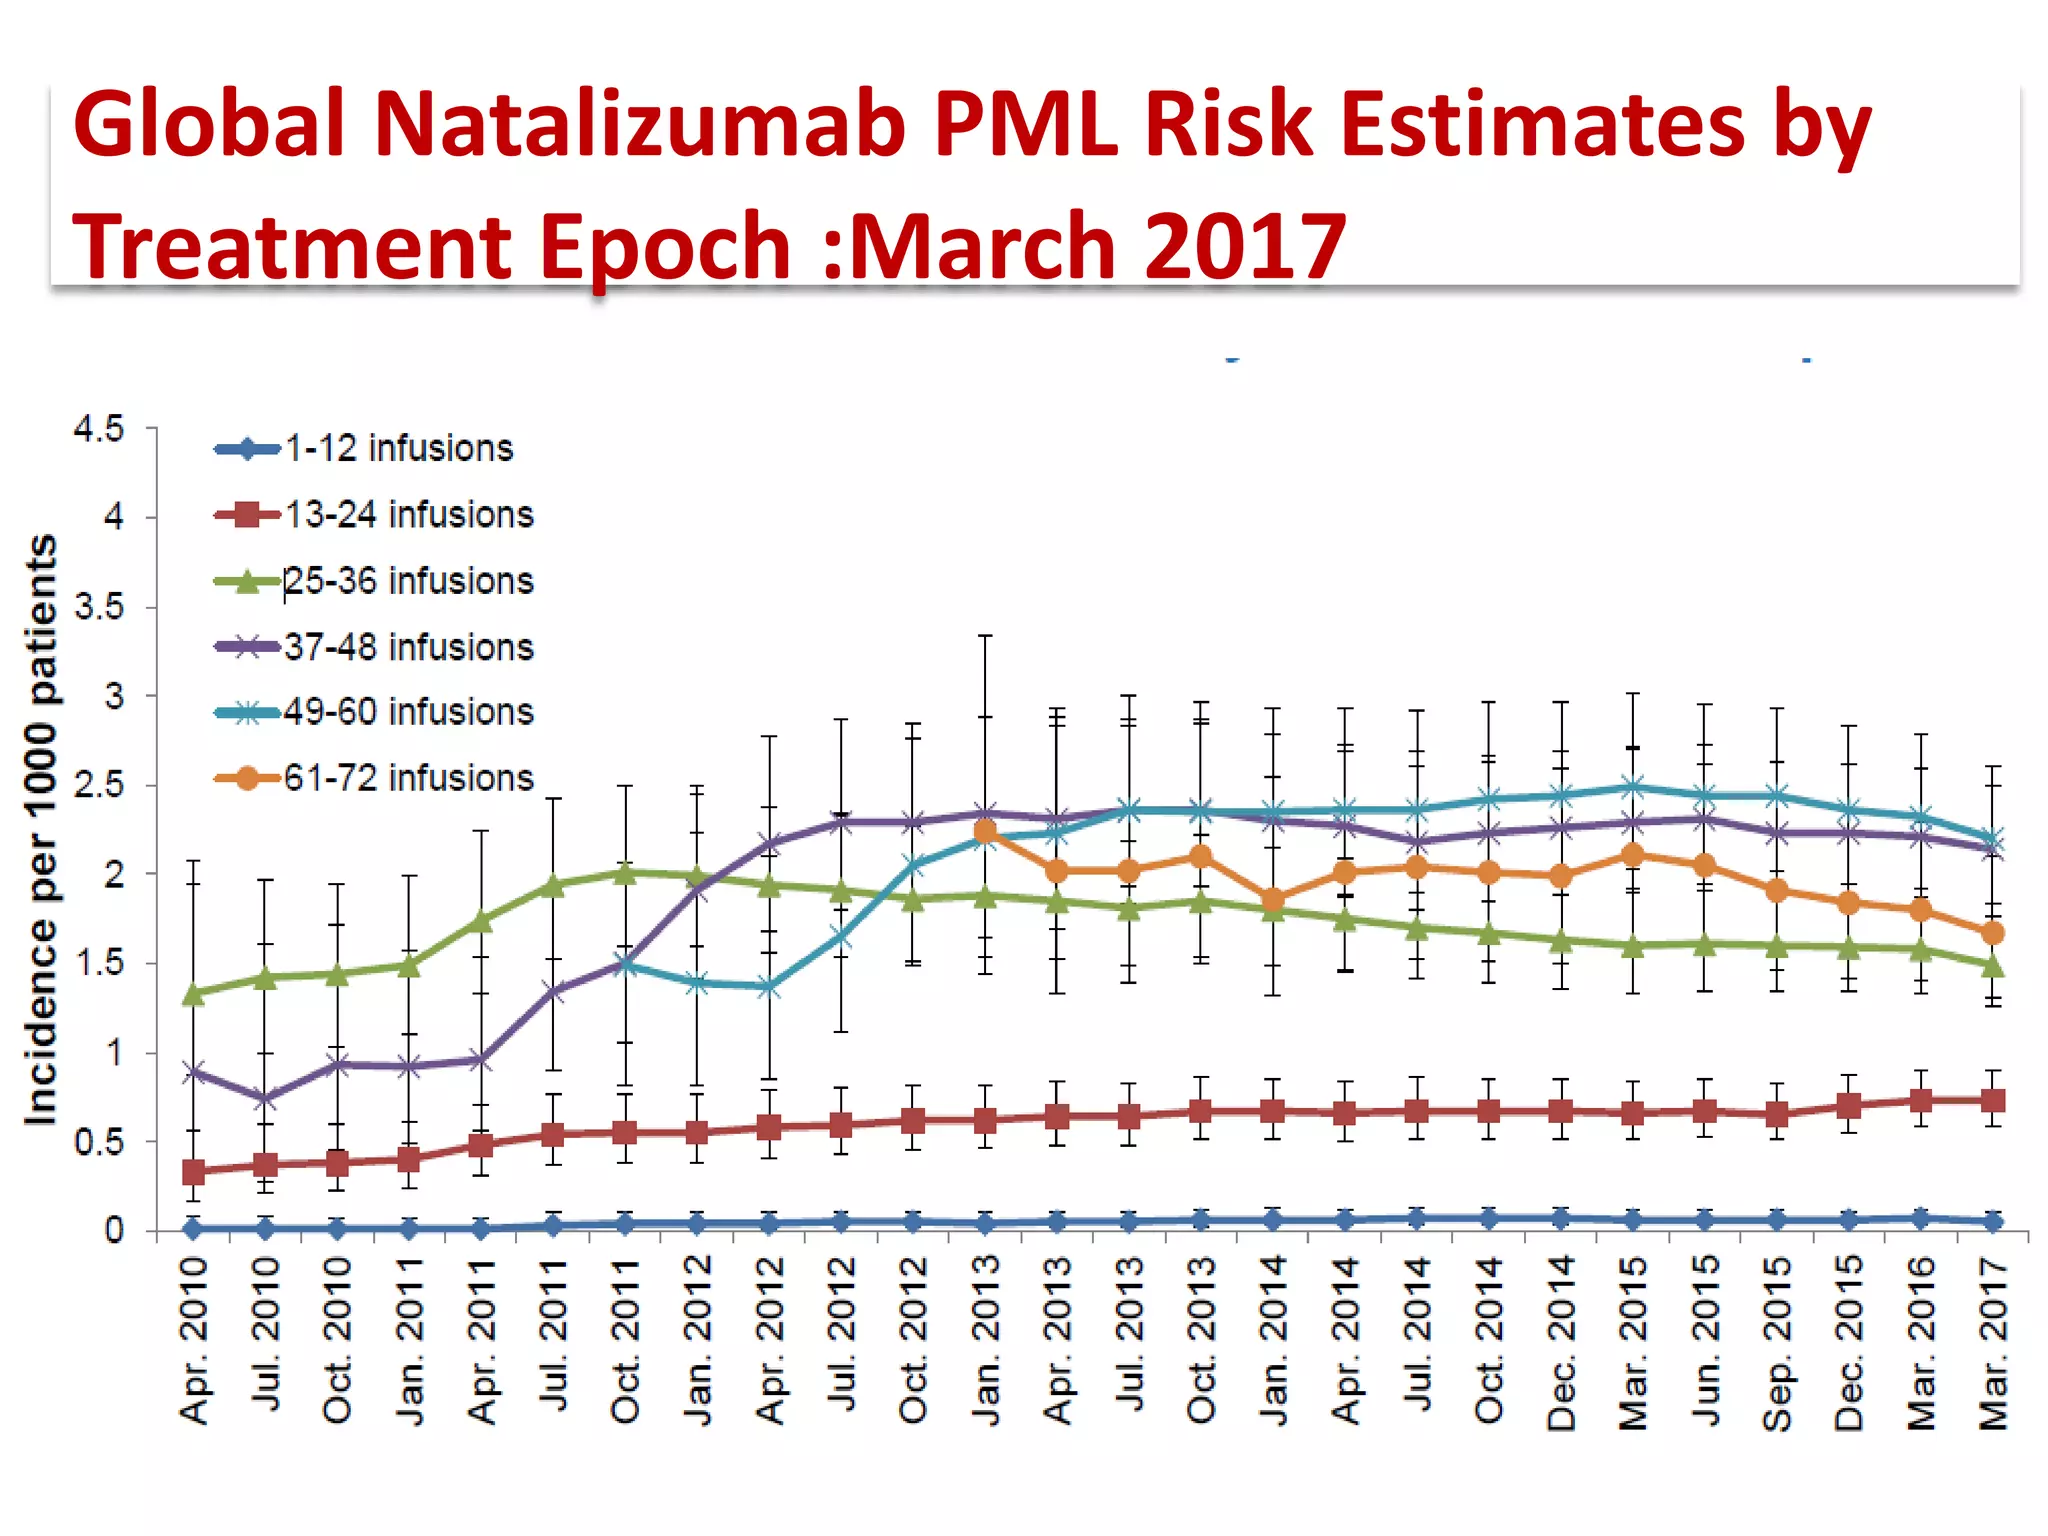

This document discusses progressive multifocal leukoencephalopathy (PML), an opportunistic infection caused by the John Cunningham virus (JCV) that leads to demyelination in the central nervous system. It highlights the epidemiology, clinical manifestations, diagnostic methods, and risk factors associated with PML, particularly in immunocompromised patients and those undergoing immunomodulatory therapies. It also presents data on the incidence of PML in patients treated with natalizumab and other therapies, addressing the relationships between these treatments and the development of PML.